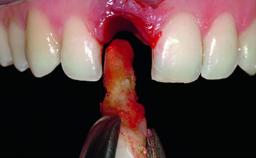

A 15-year-old male patient was referred to us by his pediatric dentist in June 2004 for evaluation of treatment options for his failing tooth 21. The patient had recently seen an endodontist for internal bleaching and been advised that there had been significant resorption and ankylosis. The patient’s mother was concerned because the tooth appeared shorter than the adjacent one. His past dental history was significant for trauma (September 2001), where the tooth had been avulsed and reimplanted. Teeth 11 and 21 had been endodontically treated.